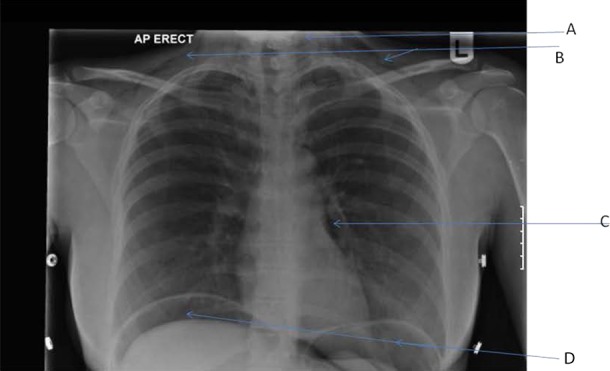

The initial chest and abdominal x-rays showed dilated loops of bowel on the right side with signs of perforation; however, this finding was not immediately apparent to the admitting team (figures 1 and 2). The patient's condition progressively deteriorated and a surgical referral was made. On review of the imaging that had been performed on admission, large volumes of free subdiaphragmatic air as well as evidence of subcutaneous emphysaema in the soft tissues of the neck were identified. The abdominal films showed dilated bowel loops and evidence of Rigler's sign.

Figure 1.

Plain anteroposterior chest radiograph extensive surgical emphysaema in the neck (A) as well as the right and left supraclavicular fossae (B). Pneumomediastinum (C) is evident in addition to obvious air under the diaphragm (D).